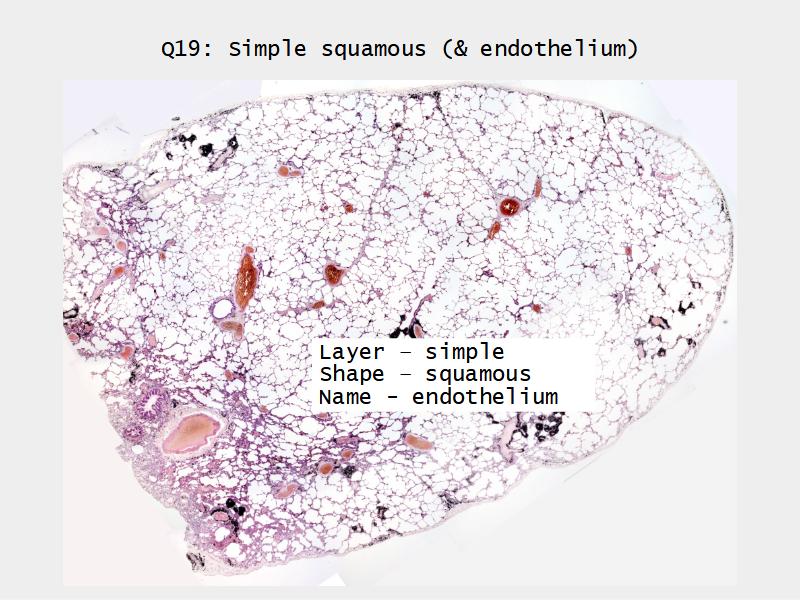

Slides: Respiratory System

- Slide 72 & 74: Lung

Lungs